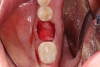

1. Minimally invasive, atraumatic extraction of the remaining tooth structure with the use of periotomes or similar instruments as well as sectioning of the tooth, when indicated, should be performed to minimize any unnecessary trauma to the thin cortical bone and surrounding soft tissues (Figure 4).

Fig 4. Atraumatic extraction of the hopeless tooth.

Figure 4